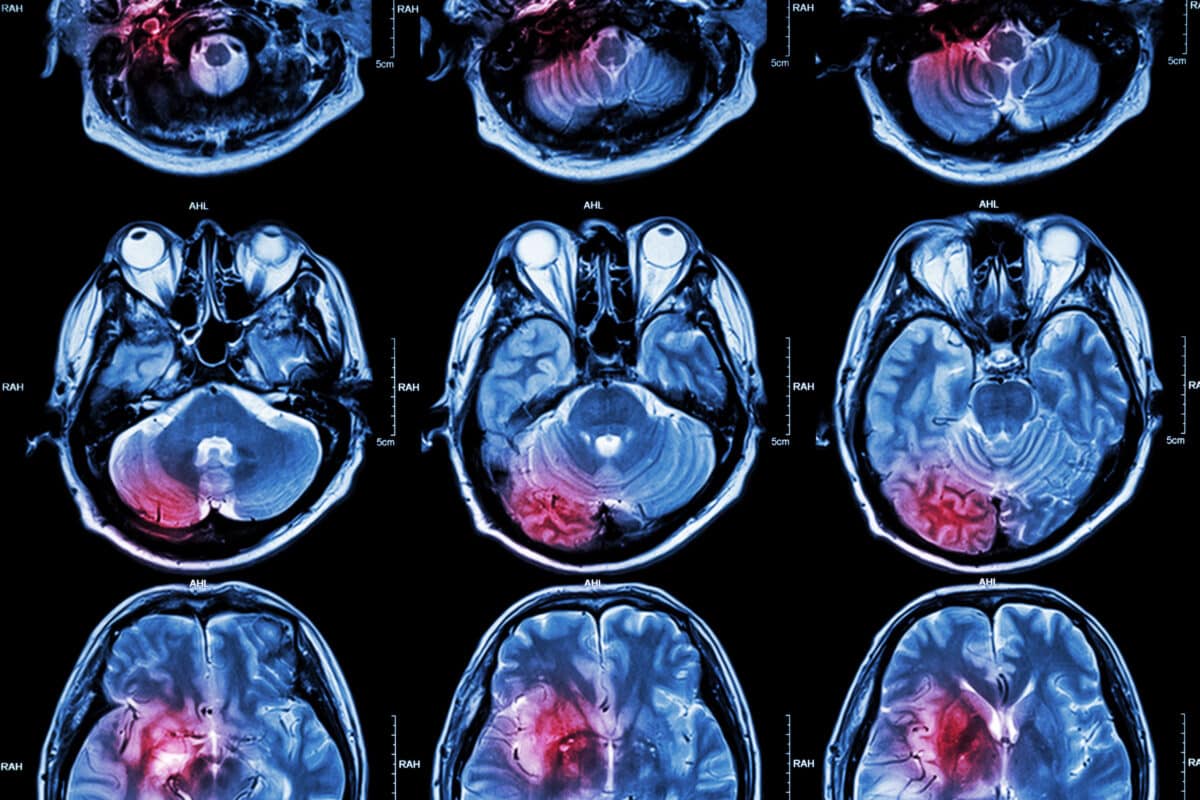

Magnetic Resonance Imaging Of Cancer Metabolism

These non-radioactive labels can be incorporated into small molecules and can then be used to study in vivo metabolic pathways in real-time. For example, carbon-13 labelled pyruvate is becoming the gold standard when it comes to the development of hyperpolarized probes. Several preclinical models have demonstrated that hyperpolarized probes can be used in the areas of neurology and oncology. Therefore, these probes can be used in conjunction with magnetic resonance imaging (MRI) and consequently have great potential towards diagnosing a disease state in personalised medicine.

The transition from preclinical models to clinical applications is a critical step in the development of hyperpolarized MRI. The first human studies using hyperpolarized [1-13C] pyruvate have shown promising results, demonstrating the potential of this technology in diagnosing and monitoring treatment responses in prostate and breast cancers. The ability to non-invasively monitor metabolic changes in real-time offers a powerful tool for personalized medicine, allowing for tailored treatment plans based on the metabolic profile of an individual’s tumour.